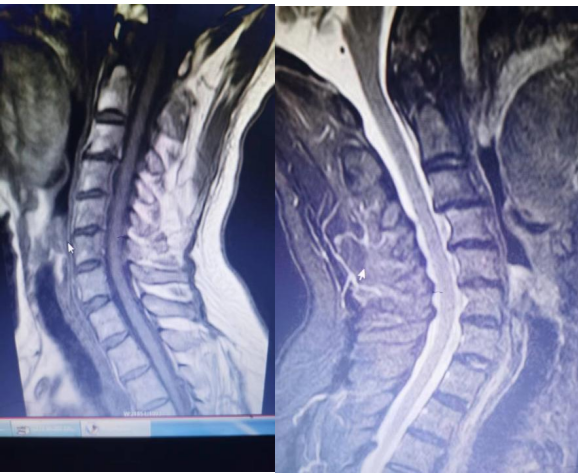

短节段横贯型脊髓炎:视神经脊髓炎谱系疾病?多发性硬化?

图片尺寸375x328